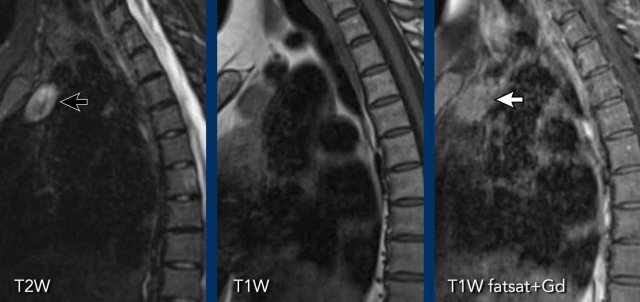

Thymic carcinoma

Case 1

These images are of a patient with a thymus carcinoma.

Notice the irregular activity in the periphery of the lesion on the PET.

The tumor was resected.

In the follow up a CT was made.

Continue with the follow up CT...

On the CT new hyperdense structures were seen in the vertebrae (arrows).

They were not there on a previous CT.

What is your opinion?

First study the images and then continue reading.

Images

Note the presence of dilated venous collaterals. This is explained by the fact that during surgery, the brachiocephalic vein is ligated, which can lead to the development of significant venous collaterals. The hyperdense structures observed in the vertebral bodies are not indicative of sclerotic metastases, but rather a consequence of venous congestion. These findings represent enhancement due to venous congestion, not metastatic disease. On a non-contrast CT, this hyperdensity would not be visible.

Continue with a later follow-up scan...

On a later follow up scan the venous congestion is not visible anymore.